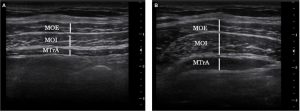

MOE: músculo oblicuo externo, MOI: músculo oblícuo interno, MTrA: músculo transverso del abdomen.